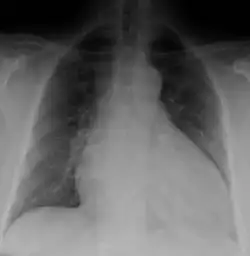

Generalized enlargement of the heart is seen upon normal chest X-ray. Pleural effusion may also be noticed, which is due to pulmonary venous hypertension.[28]

The electrocardiogram often shows sinus tachycardia or atrial fibrillation, ventricular arrhythmias, left atrial enlargement, and sometimes intraventricular conduction defects and low voltage. When left bundle-branch block (LBBB) is accompanied by right axis deviation (RAD), the rare combination is considered to be highly suggestive of dilated or congestive cardiomyopathy.[29][30] Echocardiogram shows left ventricular dilatation with normal or thinned walls and reduced ejection fraction. Cardiac catheterization and coronary angiography are often performed to exclude ischemic heart disease.[28]